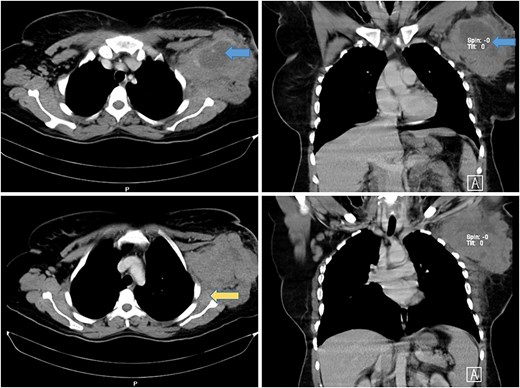

A computed tomography (CT) scan revealed a necrotic soft tissue mass (13.5 × 9.8 × 8.2 cm) infiltrating anterior chest wall muscles, subscapularis muscle, adjacent skin, and subcutaneous fat, with ipsilateral axillary and supraclavicular lymphadenopathy, consistent with T4N3M1 breast cancer (Fig. 1). Laboratory tests showed microcytic hypochromic anemia (hemoglobin: 9.3 g/dL) and a normal leukocyte and platelet count. A biopsy of the mass with immunohistochemistry confirmed diffuse large B-cell lymphoma (DLBCL) with strong CD20 positivity (Fig. 2).

Axial and coronal CT scan of the chest showing a large mass in the left axillary tail of the breast with areas of necrosis (blue arrows) with involvement of anterior chest wall muscles and infiltration of the left subscapularis muscle (yellow arrow).